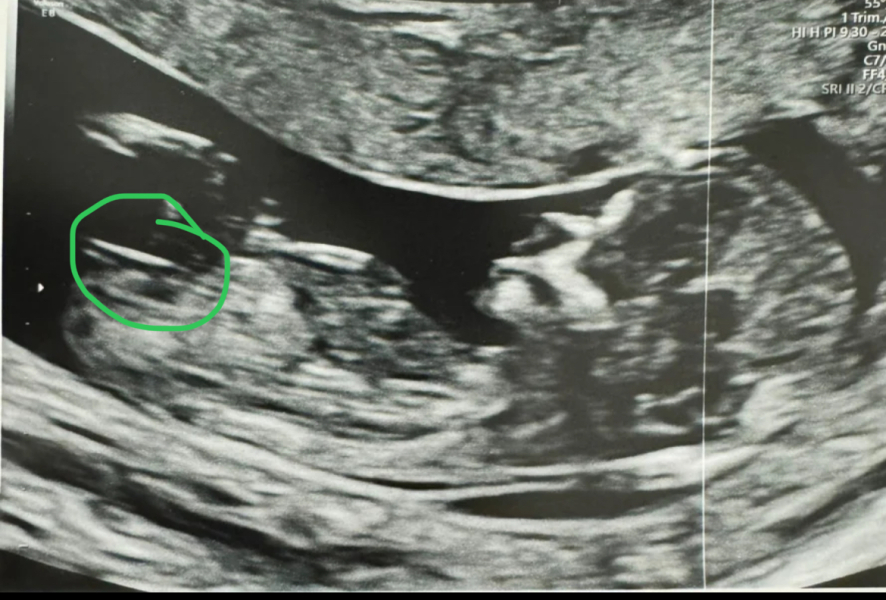

peardeer · 19/04/2024 19:20

Thank you for asking 🌈 It went perfectly 🥹🤍 I can't believe it. This is officially the furthest we have ever got. Feeling so emotional and so grateful x

And a very clear nub! Are you finding out?

@AppleTree16 I would love to know! A few people have said clear nub but I have no clue! What do you think it is? X

@peardeer I think it's a girl!

@CluelessInLondon someone else has said this! I would love either but my husband would love a girl 🌈🤍

@peardeer looks very girly to me! How many weeks are you? If you’re 12ish weeks it could still change and move up though. (I only found out this fact a few weeks ago!)

@Bee49 I'm 13+3, I still can't work out where the numb is 😂

@peardeer I’m definitely voting girl! Very inexperience but think it’s here? (Just waiting for someone to tell me I’m all wrong 😂)